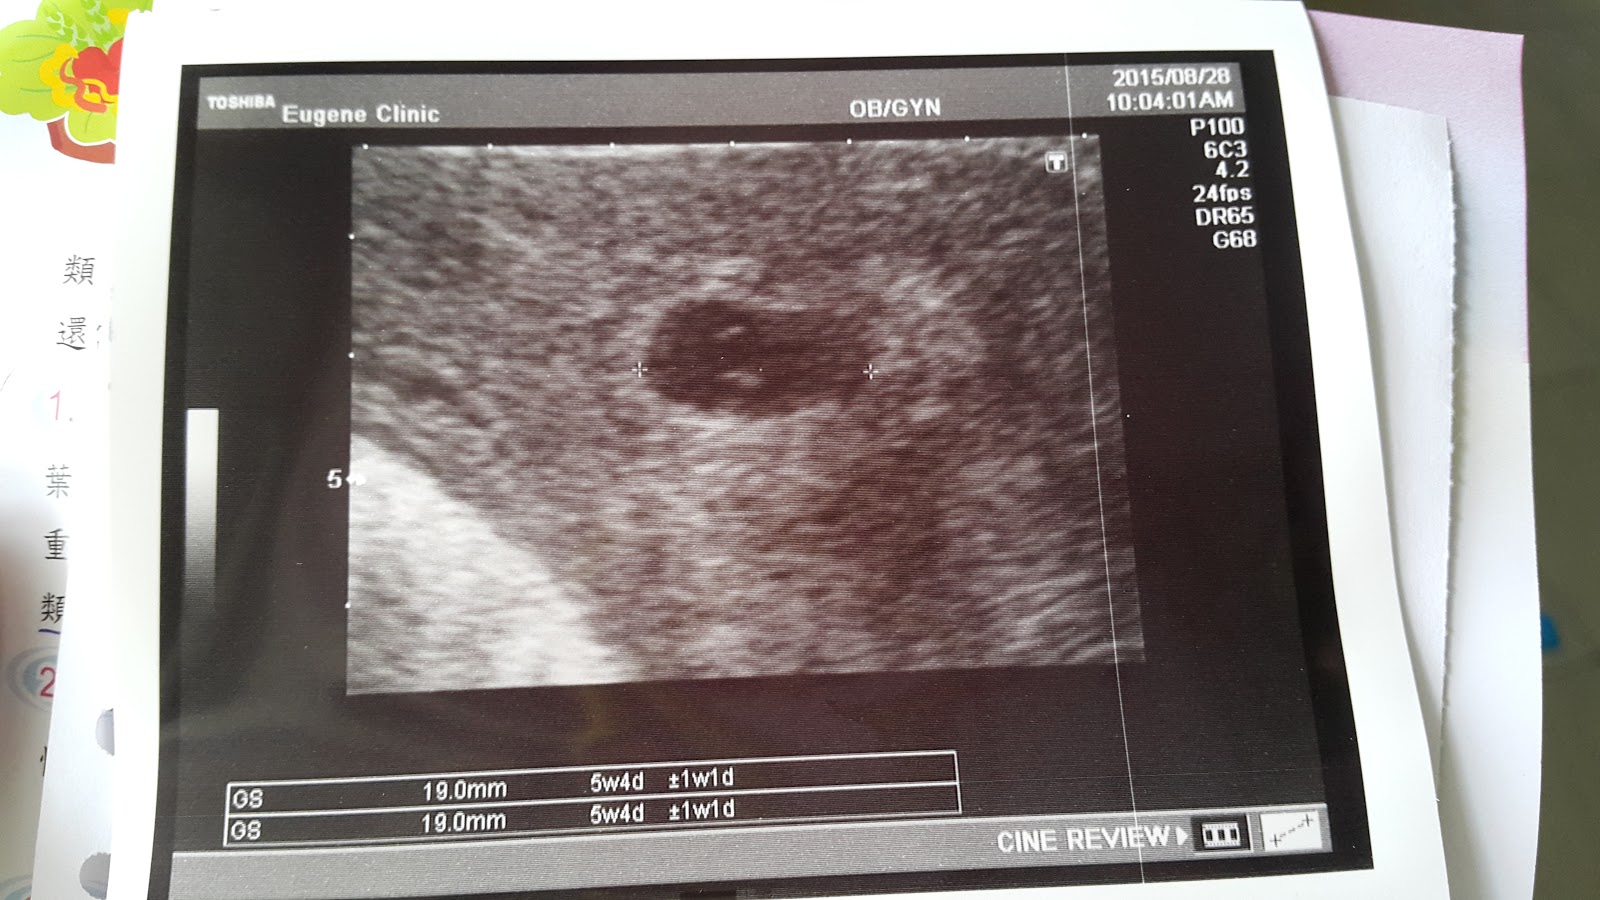

星期一驗的孕,星期五來醫院檢查

現在是一個1.9cm的小黑點

醫生說3週後再來,應該就會有心跳了

回到家很緊張拿著Leo當時的超音波照片來比對,應該是正常的大小吧~~